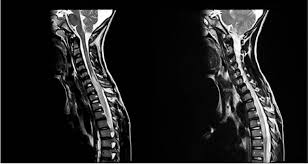

Pdf An Approach To The Diagnosis Of Acute Transverse Myelitis Andrey De Marchi Academia Edu

Pdf An Approach To The Diagnosis Of Acute Transverse Myelitis Andrey De Marchi Academia Edu from 0.academia-photos.com